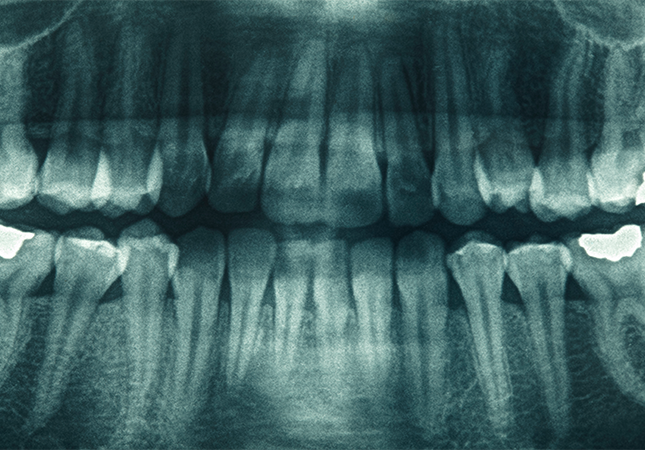

Tüm dişlerin görüntülenmesi ve doğru teşhisi koyabilmek için Denta Home’da panaromik röntgen kullanıyoruz.